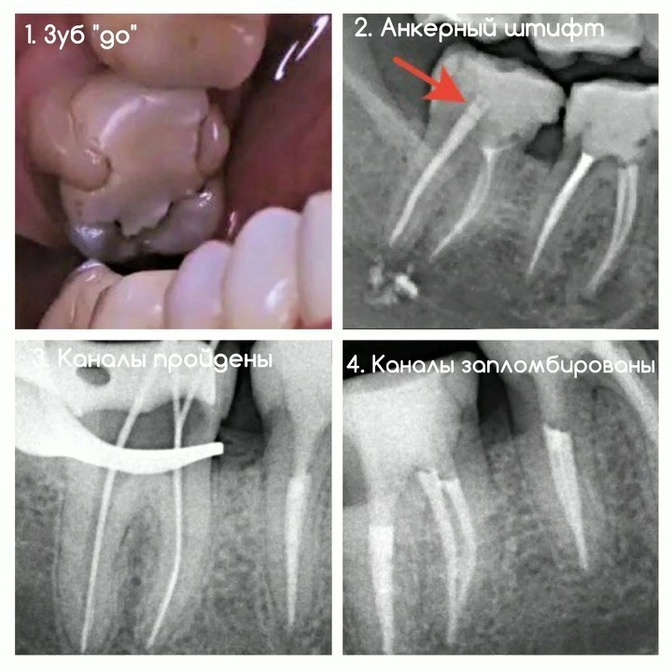

Клинический случай: перелечивание "красного зуба"

Если кратко, то так раньше лечили пульпиты.

Корневые каналы пломбировали резорцин-формалиновой пастой, из-за которой зуб окрашивался в розовый или красный цвет и становился хрупким, как стекло.

Зуб — "семерка".

Пломба несостоятельная, в каналах та самая паста, цемент и анкерный штифт.

Это металлический стержень для укрепления и восстановления сильно разрушенных зубов.